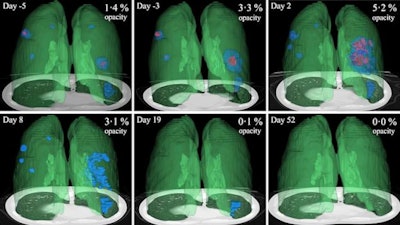

After verifying the AI lung segmentation results, radiologists then manually segmented the lung opacities and noted the opacity subtypes. Next, the researchers employed generalized temporal curves to correlate the CT data with lab measurements such as blood cell count and procalcitonin levels. 3D visualizations were also used to reconstruct the evolution of COVID opacities.

3D image visualizations show the evolution of COVID opacities over the course of the disease. Images courtesy of Nvidia.

3D image visualizations show the evolution of COVID opacities over the course of the disease. Images courtesy of Nvidia.The researchers found that lung opacities appeared in an average of 3.4 ± 2.2 days prior to symptom onset and peaked an average of 0.6 ± 3.1 days after symptoms began. Ground-glass opacity onset was earlier, and it resolved later than consolidation, according to the authors. As for lab results, lactate dehydrogenase and C-reactive protein peaked earlier than procalcitonin and leukopenia.